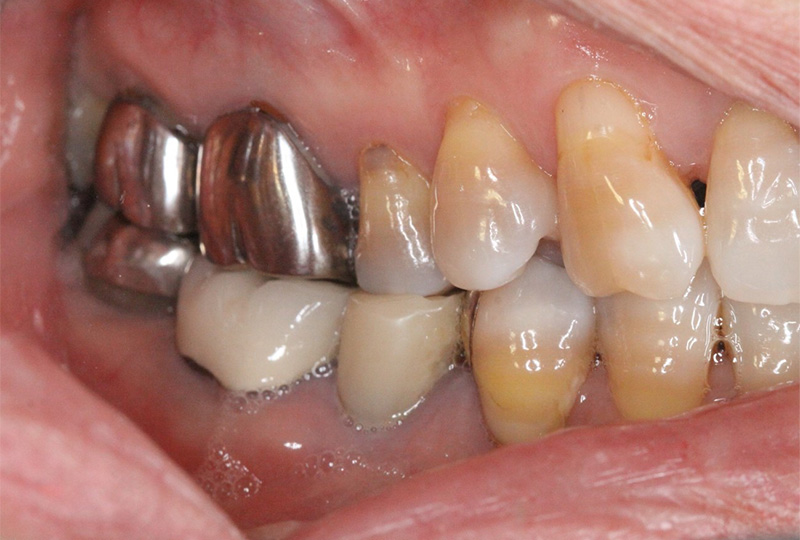

『歯のひび(歯根破折)』など通常であれば抜歯と言われるような歯の保存や歯を失った所に親知らずなどを移動させる『歯の移植』など一般の歯科医院では行わない特殊な治療も行なっております。